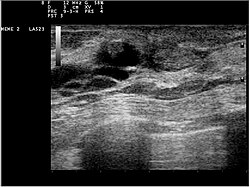

Файл:Ultrasound 12070I25 intraductal papilloma nevit.jpg

Ультразвуковое исследование папилломы